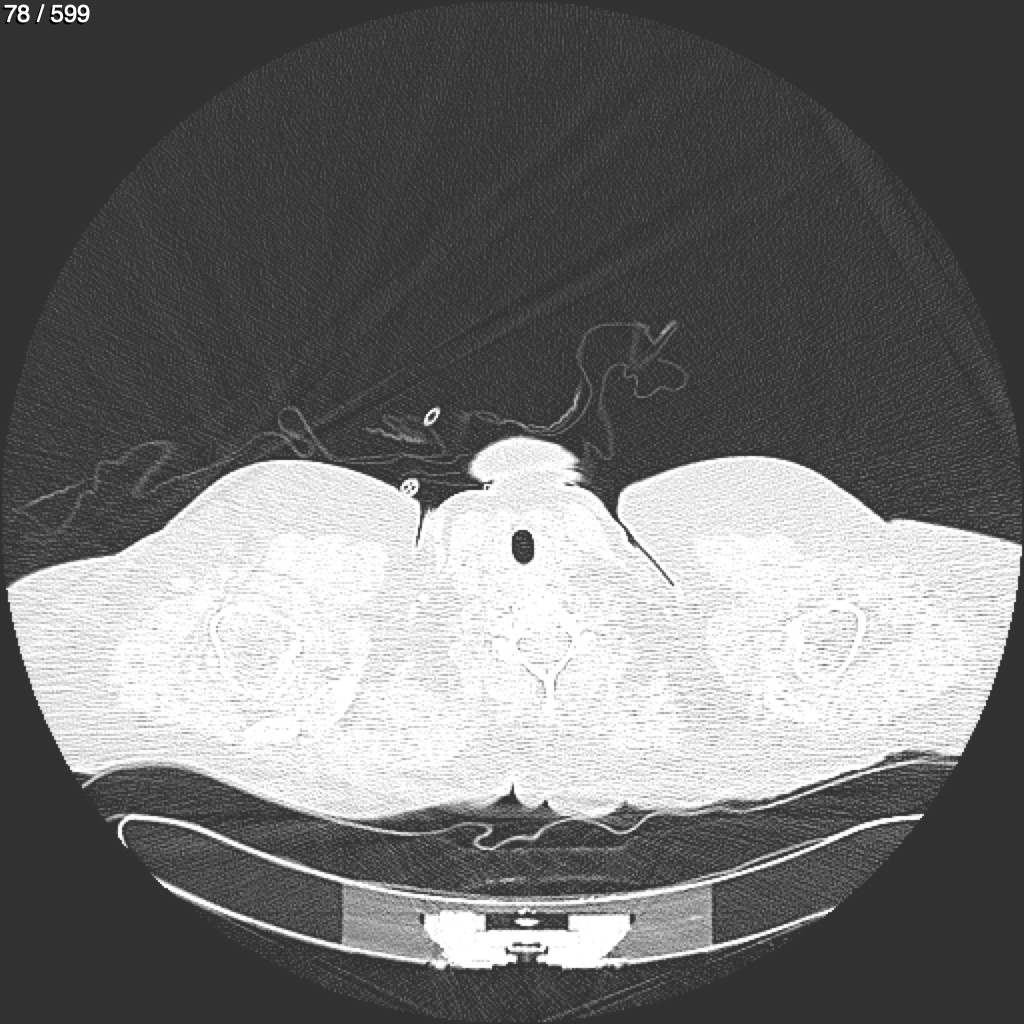

Home G​l​o​r​i​a​ ​G​l​a​d​y​s​ ​B​e​a​s​l​e​y​ ​-​ ​T​ó​r​a​x​ ​T​o​r​a​x​_​S​i​m​p​l​e​ ​(​A​d​u​l​t​o​)